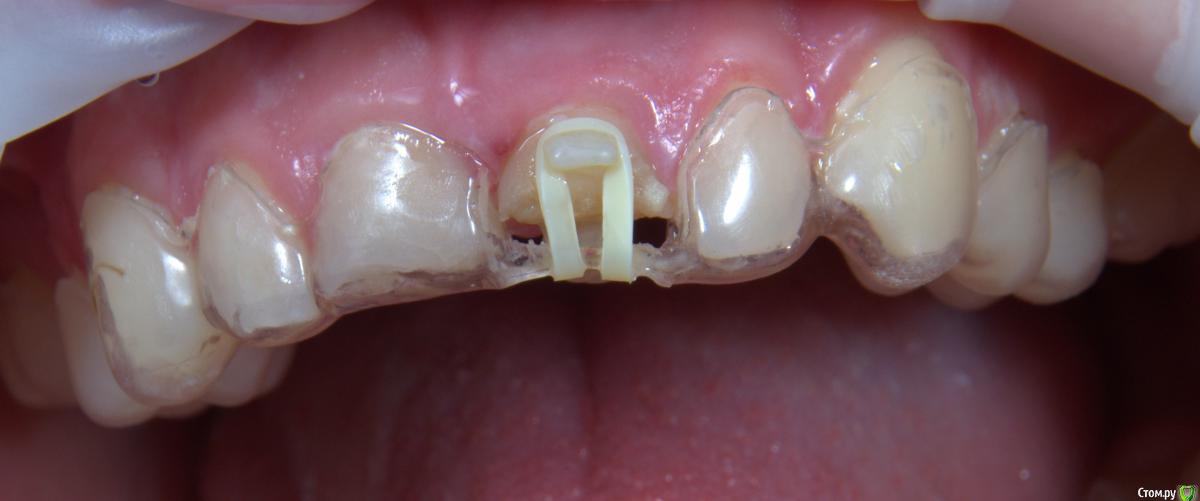

Хью Крейн Опубликовано 11 августа, 2017 Поделиться Опубликовано 11 августа, 2017 Композит на небной поверхности не мешает окклюзии? Ссылка на комментарий

kamranchick Опубликовано 11 августа, 2017 Автор Поделиться Опубликовано 11 августа, 2017 Композит на небной поверхности не мешает окклюзии?мешает, а как быть?) Ссылка на комментарий

Art 7 Опубликовано 11 августа, 2017 Поделиться Опубликовано 11 августа, 2017 ставишь стекловолоконную балку между апроксимальных поверхностях соседних зубов) Ссылка на комментарий

kamranchick Опубликовано 11 августа, 2017 Автор Поделиться Опубликовано 11 августа, 2017 ставишь стекловолоконную балку между апроксимальных поверхностях соседних зубов)Спасибо Артурчик)Попробуем так))) просто шатается сильно, страшно трогать пока что) Ссылка на комментарий

1586Doc Опубликовано 11 августа, 2017 Поделиться Опубликовано 11 августа, 2017 (изменено) Это обычная силиконовая каппа ?вытягиваем, потом стабилизация ? Как на долго? Изменено 11 августа, 2017 пользователем 1586Doc Ссылка на комментарий

kamranchick Опубликовано 11 августа, 2017 Автор Поделиться Опубликовано 11 августа, 2017 Это обычная силиконовая каппа ?вытягиваем, потом стабилизация ? Как на долго?капу сделали вакуум формером, помоему она пластмассовая вроде. стабилизация 2-3 месяца... Ссылка на комментарий